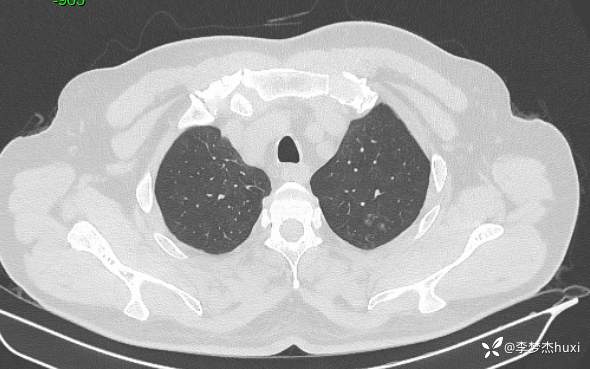

男性48岁,咯血3小时,咯血病因?

主诉:咯血3小时

简要病史:患者于入院前3小时无明显诱因出现咯血,为鲜红色,量较多,约10ml,伴胸闷、压气,伴咳嗽,无明显咳痰。

体格检查:T36.2℃,P110次/分,R20次/分,BP250/130mmHg。神清,呼吸平稳,浅表淋巴结不大,双肺叩清音,双肺未闻及干湿性啰音,心率110次/分,律齐,无杂音。腹部平坦,软,全腹无压痛,无反跳痛及肌紧张,肝脾肋下未触及,双下肢无水肿。

辅助检查:胸部CT:双肺炎症,双肺纹理增多,主动脉及冠状动脉钙化,主肺动脉稍增粗,右侧肾上腺点状高密度影,考虑脂肪肝。

临床诊断:肺炎咯血